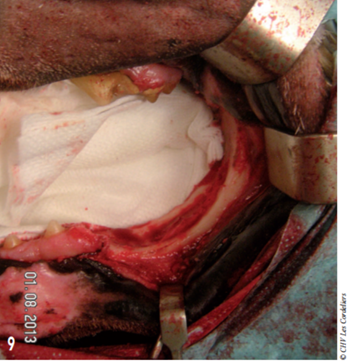

L’ostectomie allait en profondeur jusqu’au canal mandibulaire (photos 9 à 12).

Pour la fermeture, les muqueuses précédemment élevées ont été refermées en deux plans, par des surjets simples de PDS 3-0 (photo 13).

Photo 9 : La dernière prémolaire et toutes les molaires ont été retirées avec l’ostectomie.

Celle-ci s’étend jusqu’au canal mandibulaire.